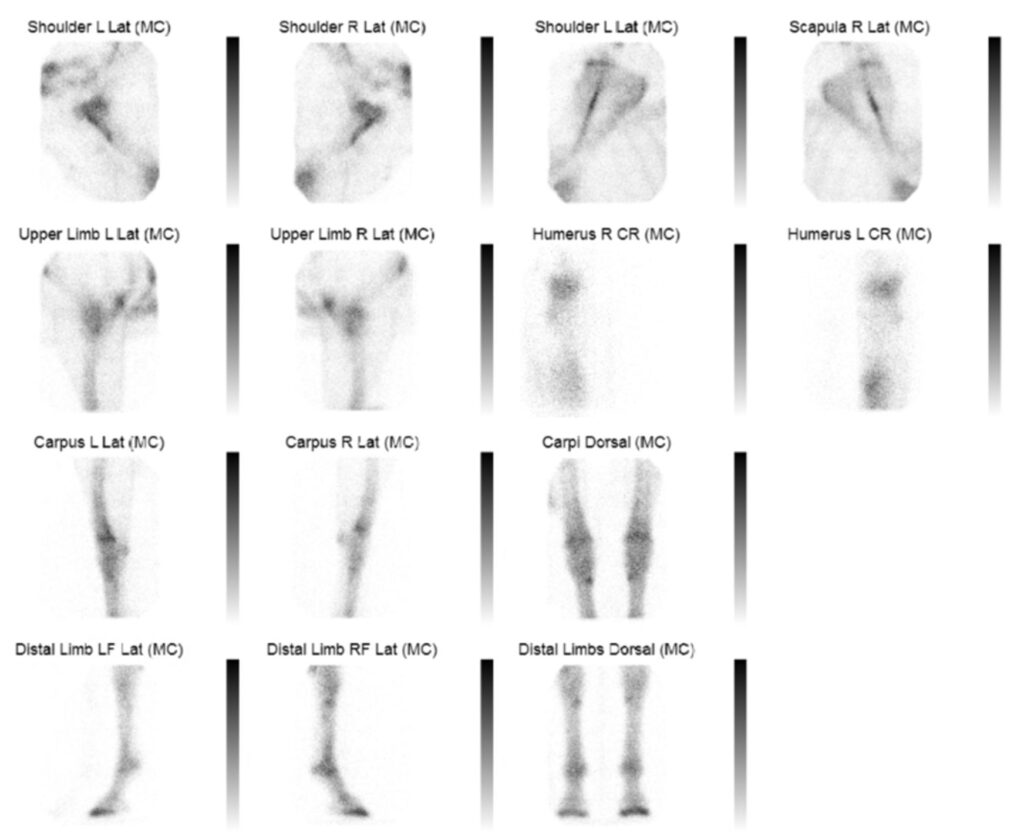

Nuclear scintigraphy was developed in 1957 and is still used in veterinary and human medicine. UWVC is the only veterinary medical clinic in Wisconsin to offer this technology for our animal patients.

Nuclear scintigraphy uses tracers - small doses of radioactive elements - that are injected and localize at specific sites in the body. A gamma camera is used to determine the location and quantity of activity in an area or organ, which allows the clinician to determine function or if an active process, like cancer or bone fracture, is occurring.

Recent upgrades to the gamma camera have improved the speed of examination and reduced stress for the patients. The gantry is quieter, making it less disruptive, and it is more mobile, so it can move around the patient rather than the patient having to shift into different positions.

Routine examinations include:

- Equine lameness localization

- Small animal metastasis screening

- Thyroid function

- Renal function (Glomerular Filtration Rate, GFR)